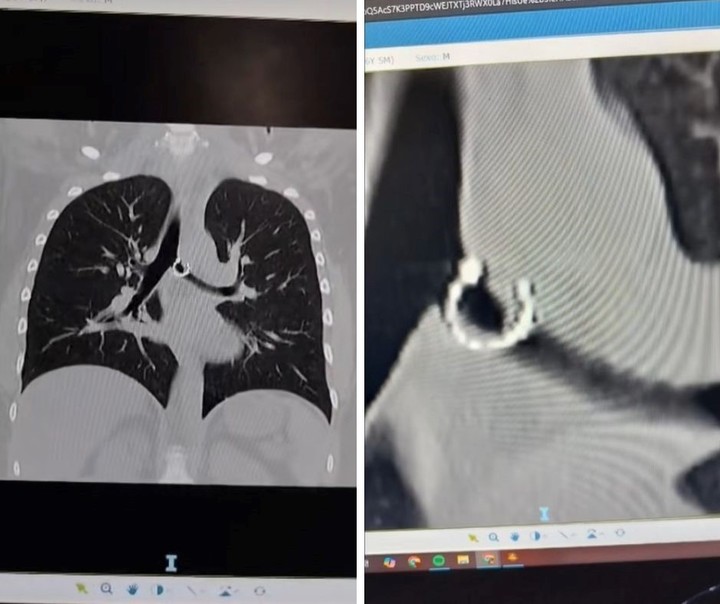

A través de este posteo, visto por más de cuatro millones de personas, aseguró haber aspirado un aro que llevaba en su nariz sin darse cuenta —lo hizo mientras dormía—, lo que le causó problemas de salud. Además, mostró radiografías e imágenes de la pieza de joyería.